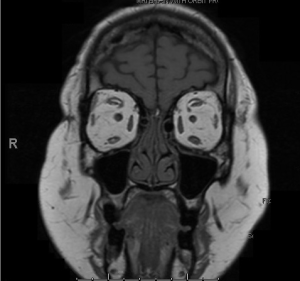

Cushing's syndrome is a known complication of systemic corticosteroids, and classically presents with cushingoid features including but not limited to increased fat deposits in the upper half of the body, thin arms and legs, acne, hirsutism, proximal muscle weakness and paper-thin skin.15 Patients with orbital involvement may display exophthalmos, periorbital soft tissue swelling, resistance to retropulsion, eyelid edema, chemosis (Figure 1), conjunctival injection, ocular hypertension, cataracts, serous retinal detachments, and globe subluxation.9,16,17 Advanced cases may show signs of congestive orbitopathy such as a relative afferent pupillary defect, constricted visual field, limitation of extraocular movements, or optic nerve dysfunction.1-9,11,18

Patients should undergo neuroimaging, which would classically show only expansion of the retro-orbital fat in patients with iatrogenic Cushing’s syndrome of the orbit. This is in contrast to patients with endogenous steroids from Cushing’s disease, which would be expected to show a pituitary abnormality in addition to the retro-orbital fat expansion. This retro-orbital fat expansion differs from other common causes of congestive orbitopathies, such as thyroid eye disease (TED), where muscle bellies are often enlarged while tendons are spared. In cases of non-specific orbital inflammation (NSOI), both muscle bellies and tendons may show enlargement. IgG4 disease classically demonstrates enlarged infraorbital canals, while changes in signal intensity could suggest other inflammatory or neoplastic processes.